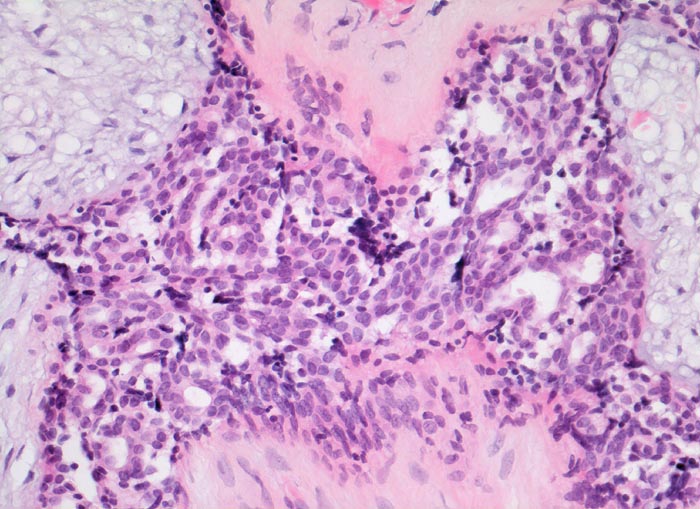

Fibroadenom der Mamma: Epithelproliferation ohne Atypie

Ausgeprägte Proliferation der epithelialen Komponente. Die proliferierten Zellen sind klein und zeigen keine zytologischen Atypien. Jeweils mehrere Zellen sind zu Strängen angeordnet und bilden ein fliessendes Muster. Zwischen den Strängen schlitzförmige Hohlräume. Das angrenzende Stroma ist zellarm und myxoid aufgelockert.

Scharf begrenzter frei beweglicher 3cm grosser derber Knoten im oberen äusseren Quadranten.

Die epitheliale Komponente von Fibroadenomen kann alle Veränderungen zeigen, welche auch im Mammaparenchym vorkommen (gutartige Epithelproliferationen, atypische Epithelproliferationen, Carcinoma in situ, invasives Karzinom...)